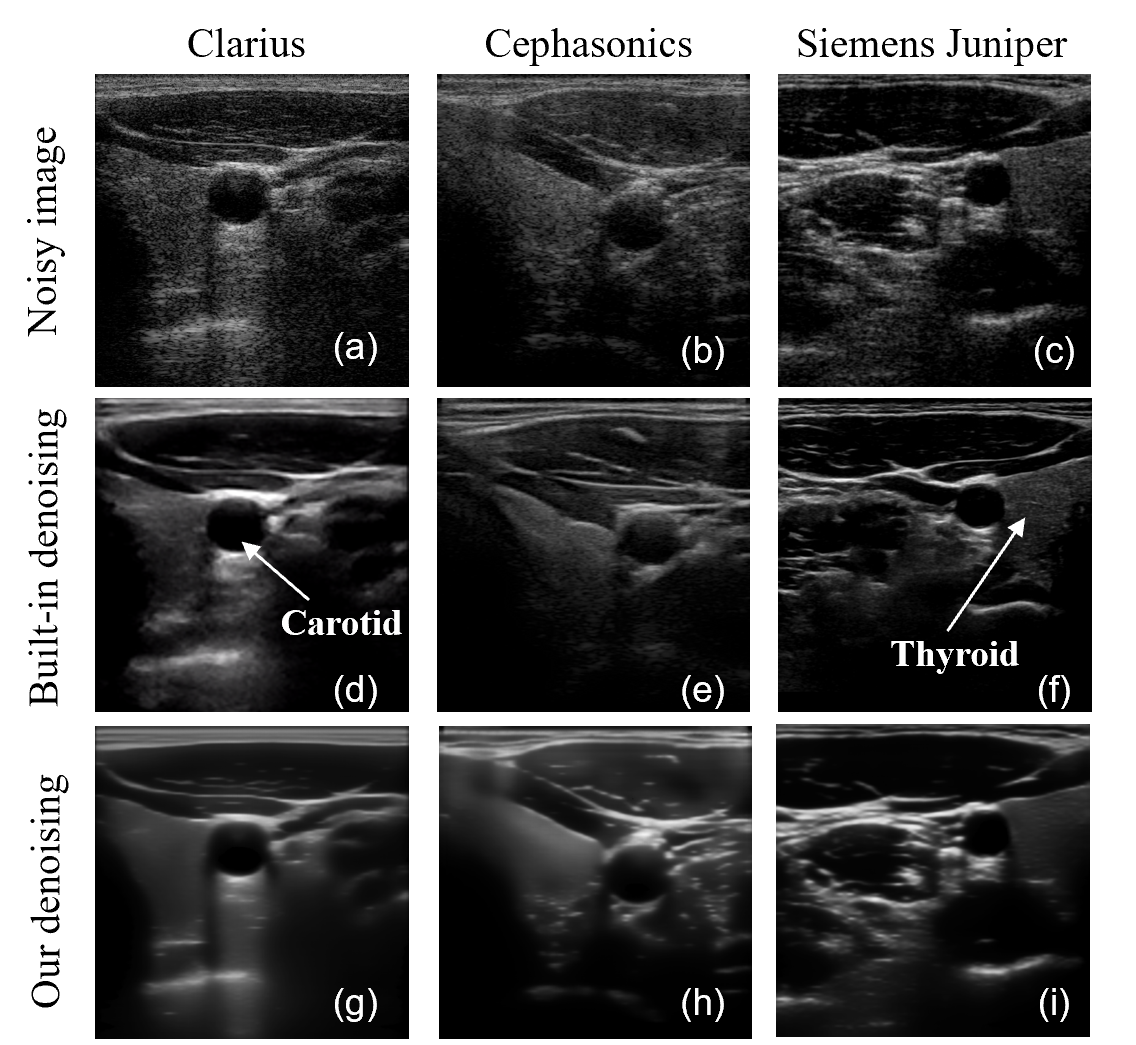

Medical ultrasound (US) is one of the most important imaging modalities in modern clinical practices due to its affordability, non-invasiveness and real-time capabilities [36, 6]. US imaging visualises internal anatomical structures by emitting high-frequency acoustic waves (typically 215 MHz) into the body and detecting echoes scattered from tissue interfaces [72]. Compared to Computed Tomography (CT) and Magnetic Resonance Imaging (MRI), US images generally suffer from lower image quality [40, 71, 8, 58], primarily due to speckle noise—one of the most prominent artefacts in B-mode imaging. This speckle noise arises from the coherent summation of echoes scattered by small-scale tissue structures (e.g., cells) and manifests as grainy patterns that degrade image clarity and contrast [41]. The degradation is especially pronounced in homogeneous regions, such as the thyroid (see Fig. 1 (a–c)), where microstructures are evenly distributed. Beyond visual degradation, speckle noise also impairs the accurate identification of both normal and pathological tissues, thereby reducing the effectiveness of computer-aided diagnosis [31] and downstream tasks like segmentation [45, 5, 30, 29, 34], registration [65, 70, 35] and anomaly detection in US images [4, 88]. To enhance diagnostic quality, modern US systems typically combine advanced hardware with tailored temporal/spatial filtering techniques to mitigate speckle. Fig. 1 (d-f) illustrates representative post-processed B-mode images acquired from three commercial US Systems—Clarius (Clarius Mobile Health, Canada), Cephasonics (Cephasonics Ultrasound, USA), and Juniper (Siemens Healthineers, Germany)—using their default manufacturer-recommended settings to image nearly the same anatomical region.

4.6.2 Cross-Device Testing on Carotid US Images

To further assess the model’s generalization capability on real US data, we collected two additional smaller datasets from different US machines (each has 180 frames), as summarized in TABLE 3. For cross-device generalization, we first applied the model—trained solely on Clarius data directly to noisy images from these unseen devices, without any fine-tuning. As shown in Fig. 11, the model still can effectively suppress speckle on these unseen domain images, demonstrating strong zero-shot generalization. As a qualitative comparison, we also included denoised results from the commercial built-in filters of the respective ultrasound devices. Compared to these built-in denoisers, our method achieves superior speckle suppression while better preserving structural detail. This is particularly evident in homogeneous regions such as the thyroid, as illustrated in Fig. 11. To further optimize performance for each unseen domain, we then performed lightweight fine-tuning on each dataset for 1000 epochs (approximately 30 minutes). The results show that the model achieves improved denoising quality even with minimal adaptation. As shown in Fig. 11, improvements in structural preservation—especially in the thyroid region—can be observed after short fine-tuning, as highlighted by the yellow rectangle for Cephasonics and the green rectangle for Siemens. These results further validate the adaptability and effectiveness of the proposed method across domains.